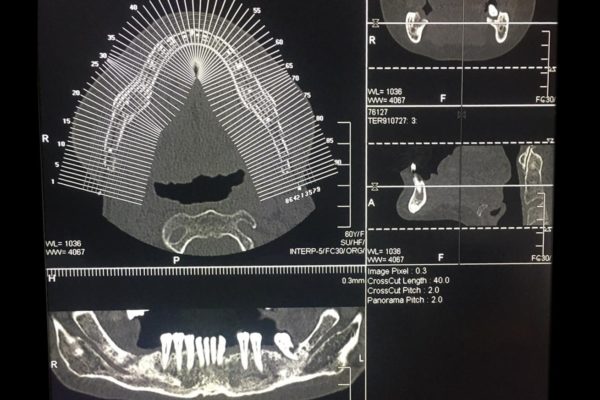

TC ARCATE DENTARIE (TC CONE BEAM 3D)

E' una nuova tecnica di Tomografia Computerizzata dedicata allo studio del massiccio facciale, in particolare delle arcate dentarie, delle articolazioni temporo-mandibolari e dei seni mascellari e che trova la sua principale applicazione nel campo implantologico, consentendo di valutare le caratteristiche morfo-strutturali, l'altezza e lo spessore dell'osso alveolare nelle sedi di interesse implantare oltre che in chirurgia orale e maxillo-facciale, nella valutazione pre-operatoria di denti inclusi, in particolare dei terzi molari, al fine di definirne con esattezza i rapporti con il canale del nervo mandibolare.

La tecnologia CONE BEAM utilizza un fascio di raggi x di forma conica che consente di acquisire un ampio volume con notevole riduzione di dose di radiazioni erogata (circa 30 volte inferiore ad una convenzionale TC).

È una metodica che permette la ricostruzione delle immagini su piani tridimensionali.